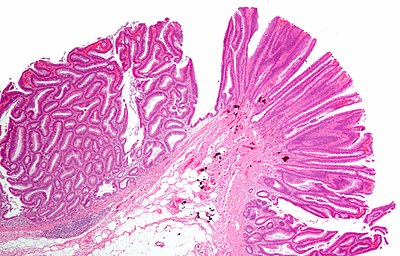

6

Diagnosis?

Peutz-Jeghers syndrome polyp.jpg

Adenocarcinoma

Colorectal mucosa within normal limits

Ganglioneuroma

Hyperplastic polyp

Inflammatory polyp

Juvenile polyp

Peutz-Jeghers polyp

Sessile serrated adenoma

Traditional serrated adenoma

Tubular adenoma

Tubulovillous adenoma

Villous adenoma

Xanthomatous polyp